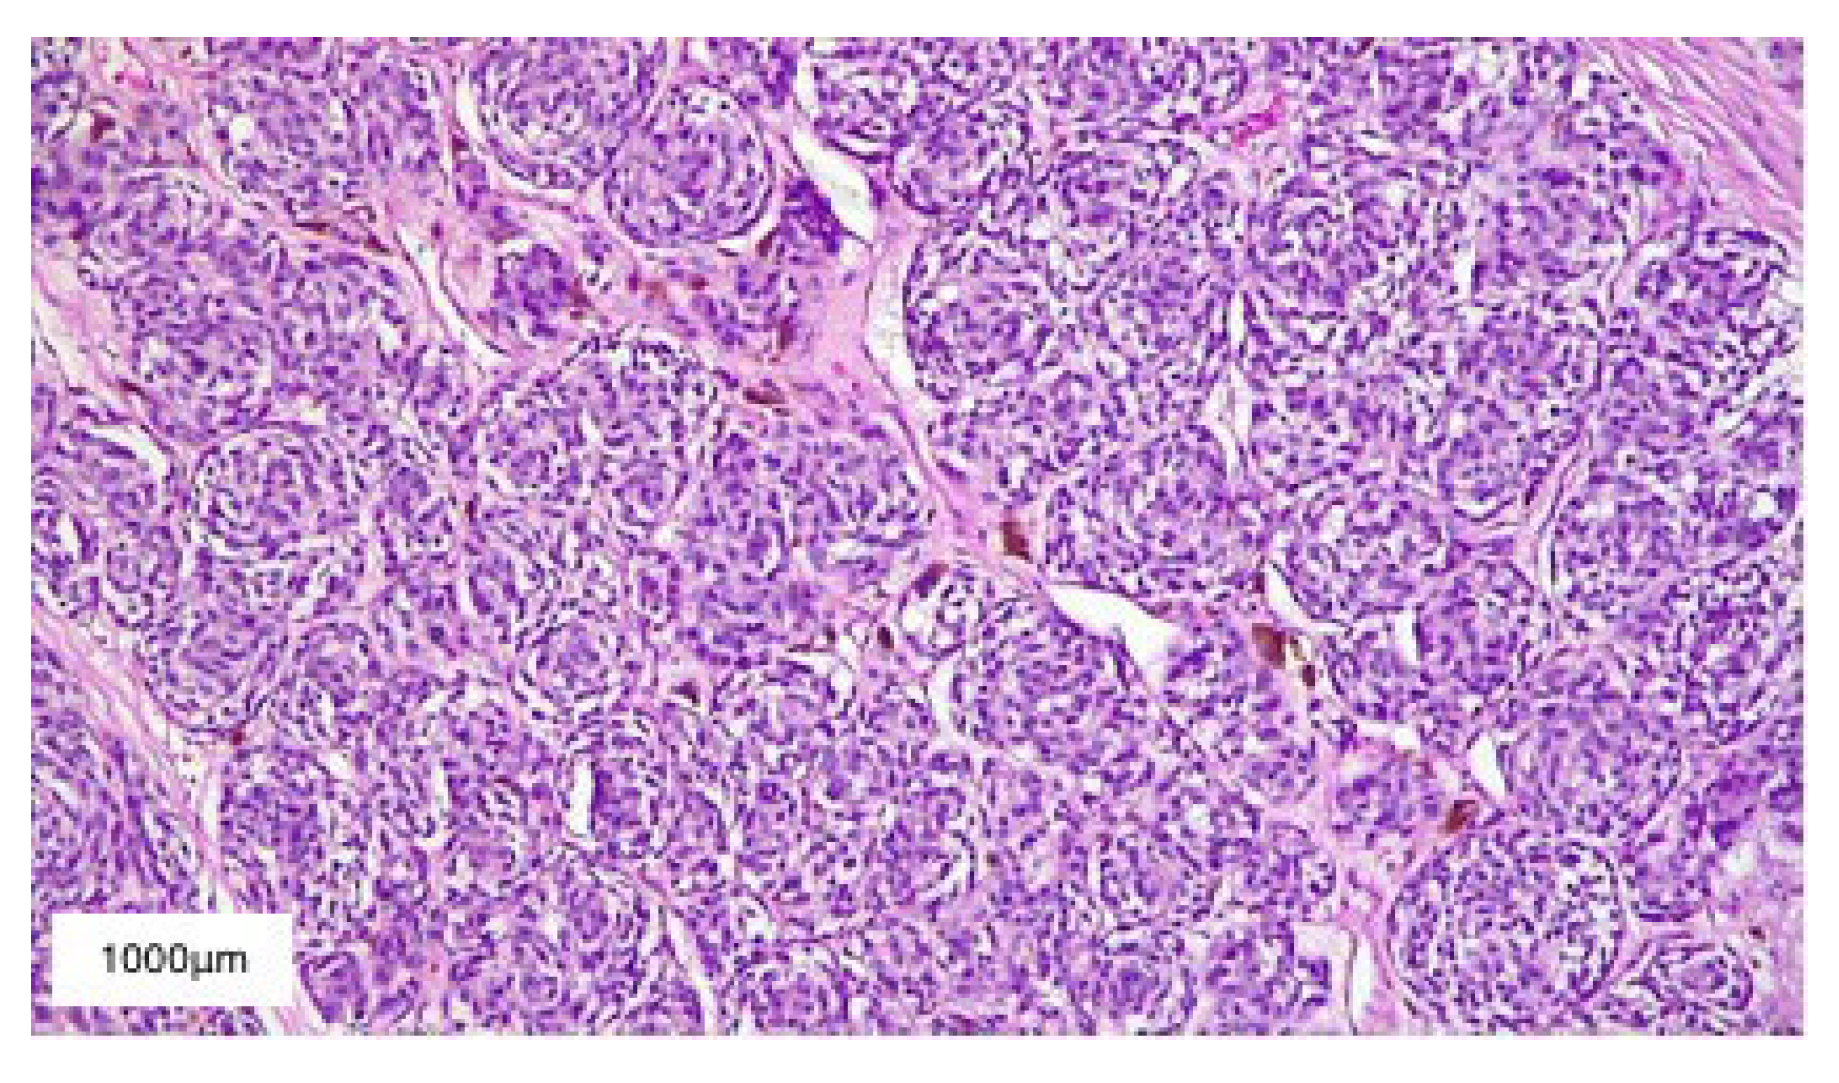

2. Case Presentation

3. Results